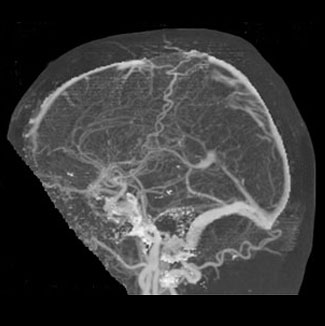

El cerebro posee un sistema de venas cerebrales, las cuales se clasifican en un grupo superficial y otro profundo, y un sistema de senos venosos,  los de la base y los senos intermedios. Todos ellos van a drenar finalmente en la vena yugular interna que emerge de la base del cr�neo y desciende formando el paquete vasculonervioso cervical.

El grupo superficial drena la corteza y la sustancia blanca subcortical, desembocando en los senos sagital superior o en los senos de la base.

El grupo profundo drena el plexo coroideo, las regiones periventriculares, el dienc�falo (talamo e hipotalamo), los n�cleos basales y la sustancia blanca profunda; desemboca principalmente en las venas cerebrales internas y en la Vena de Galeno o Cerebral Mayor

Venograma cerebral comparese con figura superior